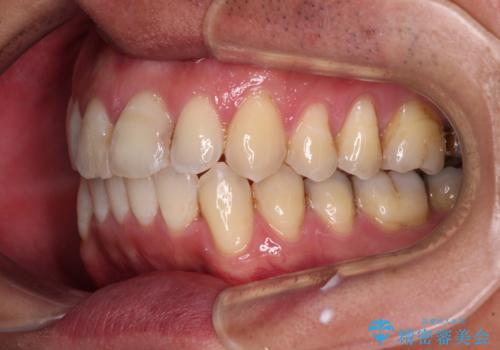

- 前歯のデコボコを気にして来院された患者様です。

下顎前歯のデコボコが特に強く、治療を早く終えることを考えるとワイヤー装置がお勧めですが、ワイヤー装置の異物感は避けたいのでインビザラインを希望されていました。

インビザラインで治療を行うか、ワイヤーで治療を行うかずっと悩んでいらっしゃいましたが、早く終わらせることを優先してワイヤー装置にて治療を行うこととしました。

下顎にワイヤー装置を装着し、暫くしたところでやはりインビザラインにて矯正治療をしたいとのことで、インビザラインに切り替えました。

短い期間でしたがワイヤー装置を使用したことでデコボコが解消されたため、インビザラインの比較的短い期間で矯正治療を行うことができました。